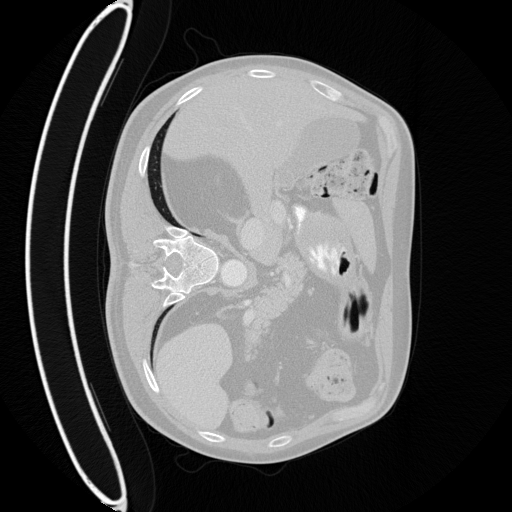

Refer to caption

(a) Image

(b) GT

(c) Ours

(d) nnUNet

(e) DSSAU-Net

(f) U-Kan

Fig. 3: Qualitative comparisons. MedCondDiff yields more accurate predictions with finer details and contours (Blue: false negative; Orange: false positive; Red: Hallucination).

To ensure fairness, we sample four segmentation masks per test case and select the best for visualization. Fig. 3 shows representative results against baselines, quantitative results shown in Table 1. MedCondDiff yields anatomically consistent masks with sharper boundaries and stronger structural fidelity across modalities.